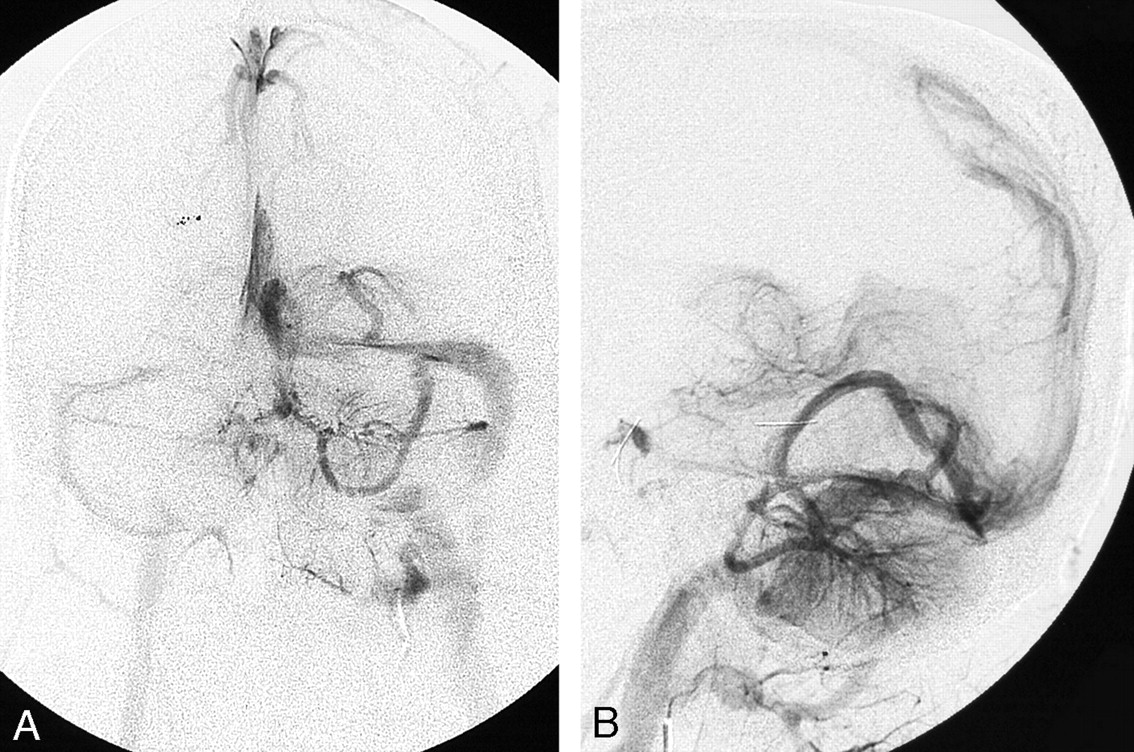

A and B, Postgadolinium axial T1-weighted MR images of a patient with a left preseptal orbitofrontal lymphatic malformation shows ipsilateral posterior fossa DVAs.

A and B, Posterior fossa DVA in another patient is confirmed angiographically. Frontal (A) and lateral (B) venous phase of left vertebral angiogram shows the left cerebellar and left occipital DVAs draining into the left transverse sinus.